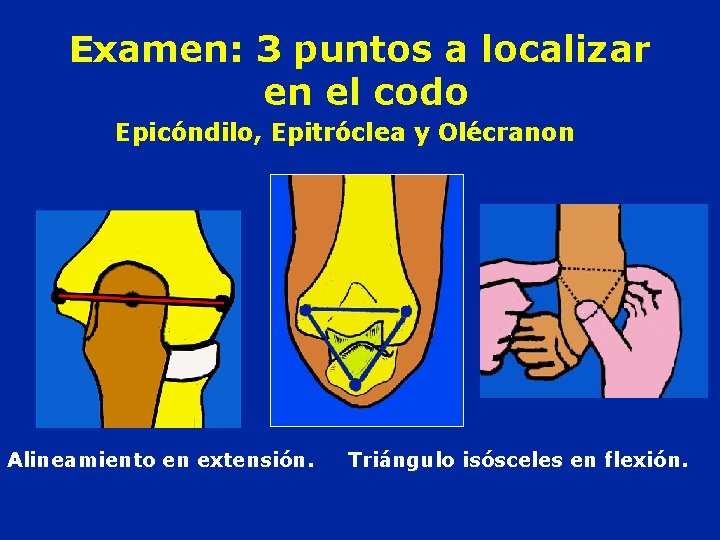

Examen: 3 puntos a localizar en el codo Epicóndilo, Epitróclea y Olécranon Alineamiento en extensión. Triángulo isósceles en flexión.

Los 3 puntos del codo delimitan un triángulo isósceles de frente Ellos están en un plano frontal

PALPACION Anterior: • Relieve de la tróclea Posterior: • Olécranon • Cúpula radial • Los 3 puntos del codo se modifican